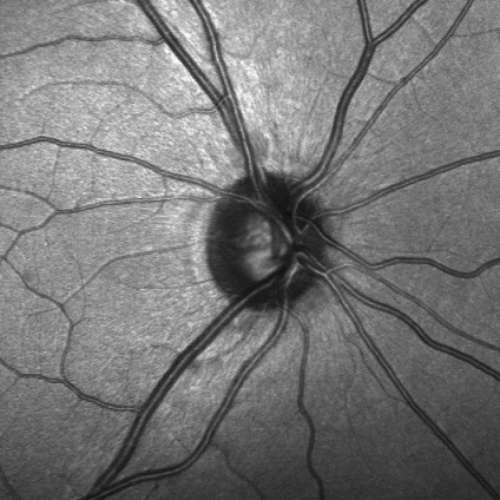

Hallazgo de células madre en el nervio óptico da luz para tratar el glaucoma

▲ A falta de esas células, el nervio óptico es incapaz de repararse a sí mismo. Foto archivo Gobierno de Canarias

Llamadas progenitoras neurales, nutren las fibras que lo forman; sin ellas, éstas empiezan a deteriorarse